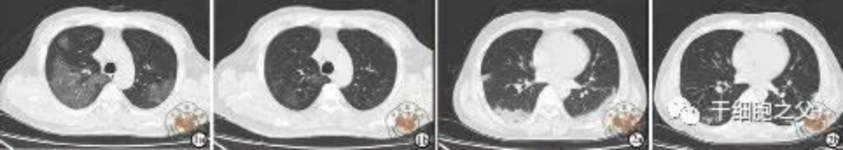

與安慰劑組相比,人臍帶間充質干細胞修復組全肺病變體積改善了10.8%,并且人臍帶間充質干細胞修復組在每一個隨訪節點都顯示出固體組分病變體積比例減少。此外,人臍帶間充質干細胞組有17.9%的患者在12個月時CT圖像變為正常,而安慰劑組沒有。

研究結果:細胞輸注后,炎癥指標改善,復查胸部CT提示雙肺病灶較前吸收,呼吸道癥狀改善,新型冠狀病毒核酸檢測連續2次陰性,治愈出院。